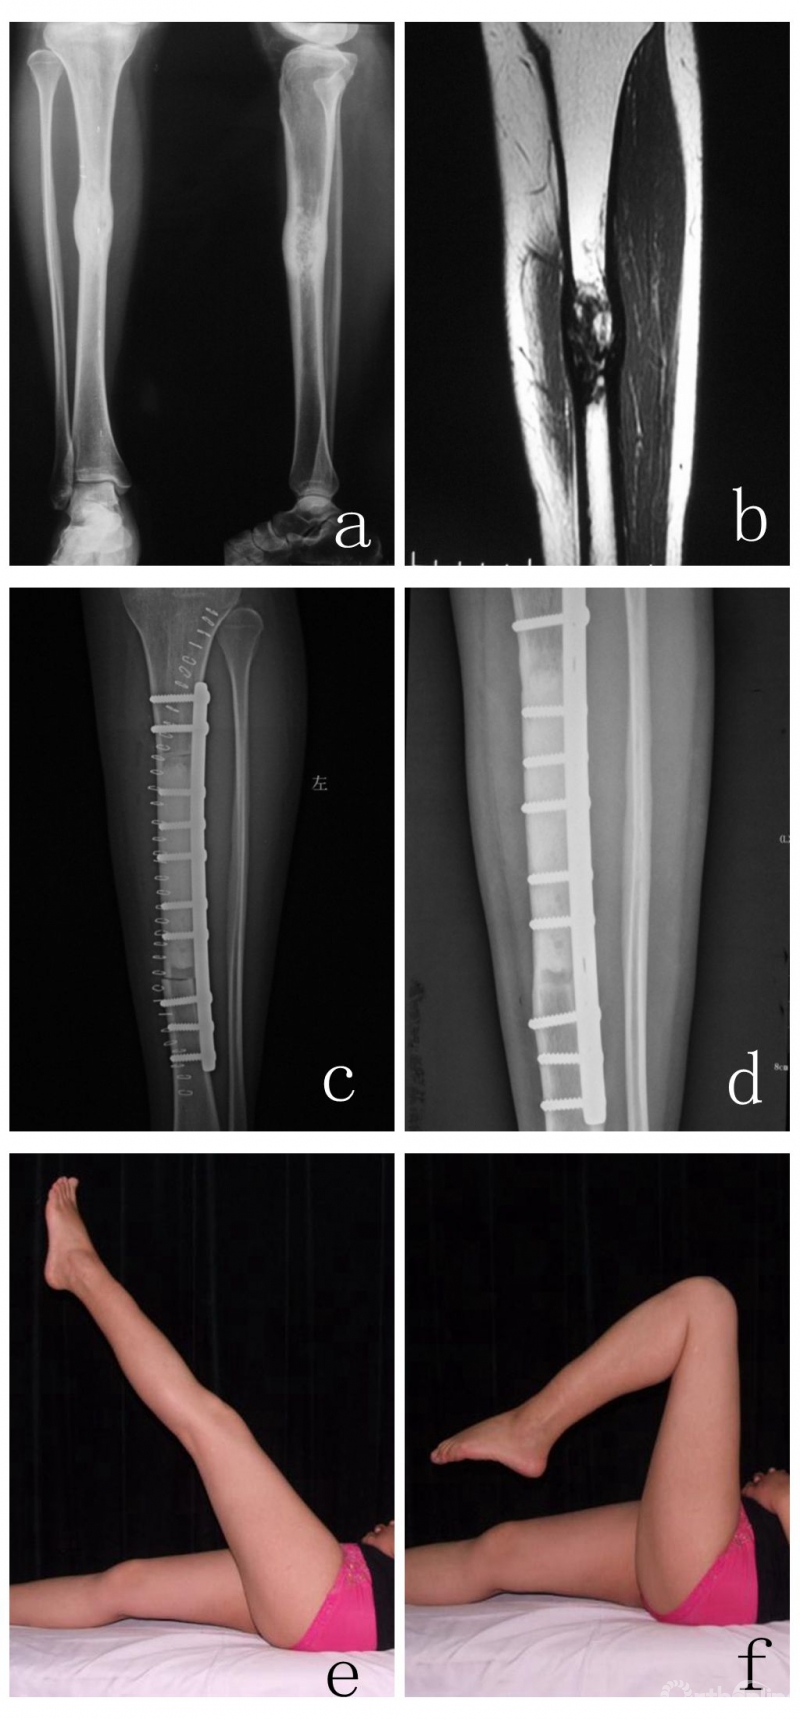

图2女,38岁,胫骨造釉细胞瘤,行瘤段截除大段异体骨重建。a 术前X线片,b,术前MRI,c, 术后X线片,d,术后4年半X线片,e,f,术后4年半功能相

29例患者两端均自然愈合(图2),5例患者为两端未愈合,其中2例患者已经因疾病死亡,1例因肿瘤复发行截肢,另外2例均为股骨干缺损重建,患者扶拐行走,不愿接受手术。另外30例患者为一个接触端未愈合,4个接触端再次手术行带血管蒂腓骨或髂骨移植,其中3例为带血管蒂腓骨,1例为带血管蒂髂骨,经过7~12个月得到愈合,5个接触端通过植自体髂骨得到愈合,愈合时间为8~23个月,其余患者均仍在等待愈合或对生活影响不大未行手术。